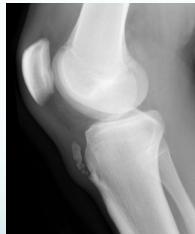

Soft Tissue and Traumatic Conditions

- Soft tissue hamartomas

- Myositis ossificans

- Stress fracture:

- Tendon avulsion injuries:

- Near hip and knee (e.g. Osgood-Schlatter)

- Infection